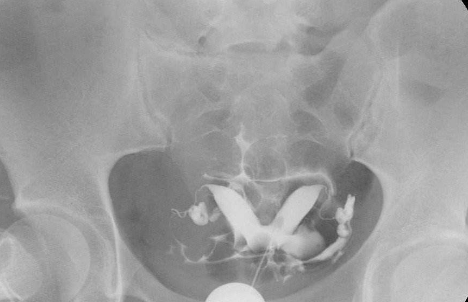

子宮輸卵管造影

A:雙角子宮根據宮角在宮底水平融合不全的程度,分為完全性的雙角子宮和不全性雙角子宮。一般情況下,雙角子宮是沒有臨床症狀,所以不易發現。有時候雙角子宮會合併有月經量多或者是不同程度的痛經。行婦科檢查的時候可以觸及宮底部是有凹陷的,一般都是通過超聲……

A:雙角子宮是子宮發育異常的其中一種,也是臨床上比較常見的。雙角子宮在臨床上根據宮角在宮底水平融合不全的程度,可分為完全雙角子宮和不完全雙角子宮。在臨床上一般並無特殊症狀,雙角子宮可有月經較多,或者伴有不同程度的痛經症狀。一般通過超聲檢查或者磁……